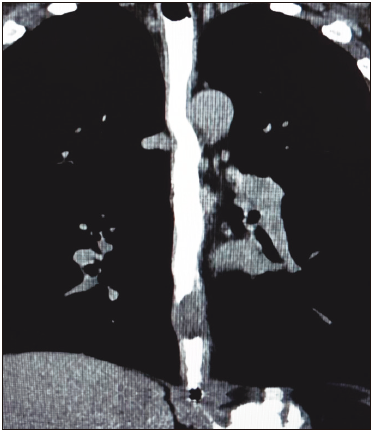

Paciente varón de 56 años, que consultó por pirosis y disfagia, indicándose la realización de una videoendoscopia digestiva alta (VEDA). Se observó en el tercio inferior esofágico una lesión elevada, erosionada, con un tamaño estimado de 20 mm, subpediculada y de aspecto subepitelial (Figura 1). Presentaba una importante dureza al tacto con el fórceps de biopsia. Se realizó una tomografía computada multislice (TCMS) de tórax, observando la lesión en la pared del tercio inferior esofágico, hipodensa y homogénea, sin compromiso del mediastino ni de órganos vecinos (Figura 2).

Figura 2.